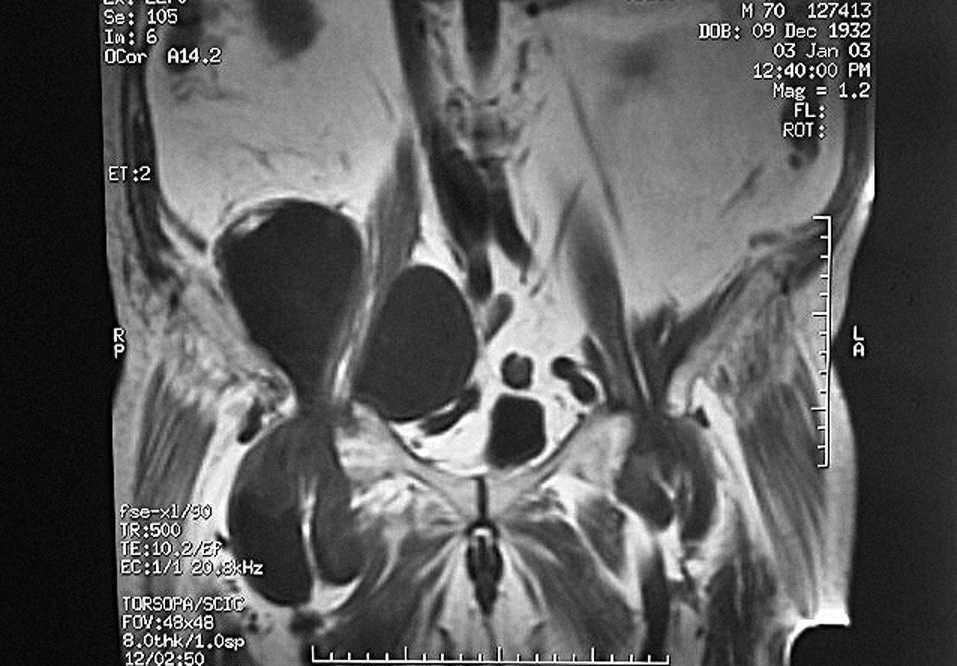

En la radiología simple se aprecia un aumento de partes blandas periarticulares e imágenes de osteólisis en cabeza femoral derecha con formaciones quísticas y geodas. Se realiza ECO abdominal, apareciendo múltiples masas retroperitoneales en ambos psoas hacia regiones ilíacas e inguinales, con compresión del paquete vascular ilíaco8. La tomografía computarizada (TC) abdómino-pélvica revela una colección de líquido en el interior del psoas, bilateral, con compresión de vasos ilíacos y vejiga urinaria. Se efectúa una RM donde se aprecian quistes sinoviales ectópicos gigantes en ambas caderas, más artropatía coxo-femoral bilateral secundaria a artritis reumatoide (fig. 1). Para descartar una posible patología infecciosa se realiza una gammagrafía con 99mTc/67Ga con el resultado de proceso inflamatorio en la zona coxo-femoral derecha, con afectación de partes blandas adyacentes y posible absceso de fosa ilíaca derecha. Los estudios con eco-doppler descartaron TVP. En el cultivo del líquido sinovial (pospunción) en un principio se aísla Staphylococcus hominis, considerándose como posible contaminante. En cultivos posteriores se aísla Staphylococcus aureus. Los marcadores tumorales (FP, CEA y PSA) fueron negativos. Presentaba un aumento de la PCR, factor reumático positivo y elevación de la velocidad de sedimentación globular (VSG), siendo el resto de la analítica normal. La serología para Brucella, Salmonella y Shigella fue negativa.

Figura 1. Corte coronal de resonancia magnética (RM) que muestra quistes sinoviales ectópicos gigantes. Se aprecia la disposición extrapélvica de los mismos y su paso a través del anillo inguinal, siguiendo el trayecto del psoas para expandirse de modo intrapélvico.